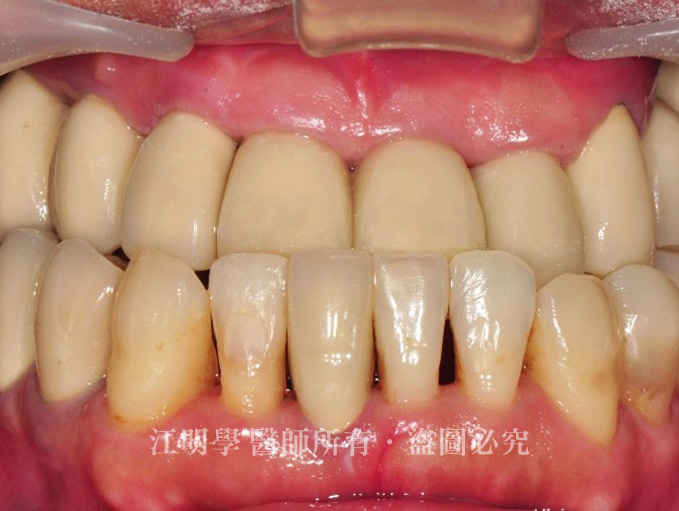

接著利用人工植牙將缺牙部分重建起來,並重新設計牙齦高度,將咬合調整到最自然美觀的位置。

治療後:配合自然牙的狀態重建植牙,讓整體更加和諧。

江先生回診時表示,現在有了一口完整健康的牙齒,不但飲食正常,身體狀況也逐漸恢復。更大的收穫,是從醫師身上獲得許多牙齒保健的知識,現在江先生終於瞭解到,飲食不但直接影響身體健康,也對情緒和精神健康有很大的關係,並表示絕對會好好保養這口新牙。